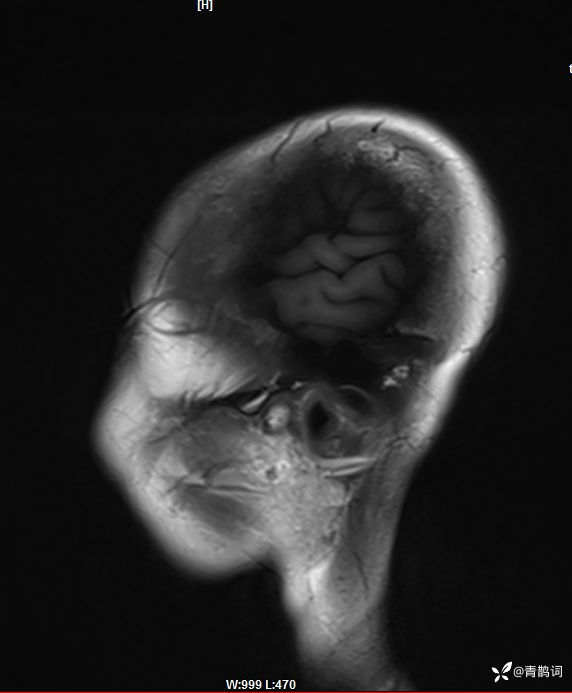

入院后完善磁共振:

矢状位: